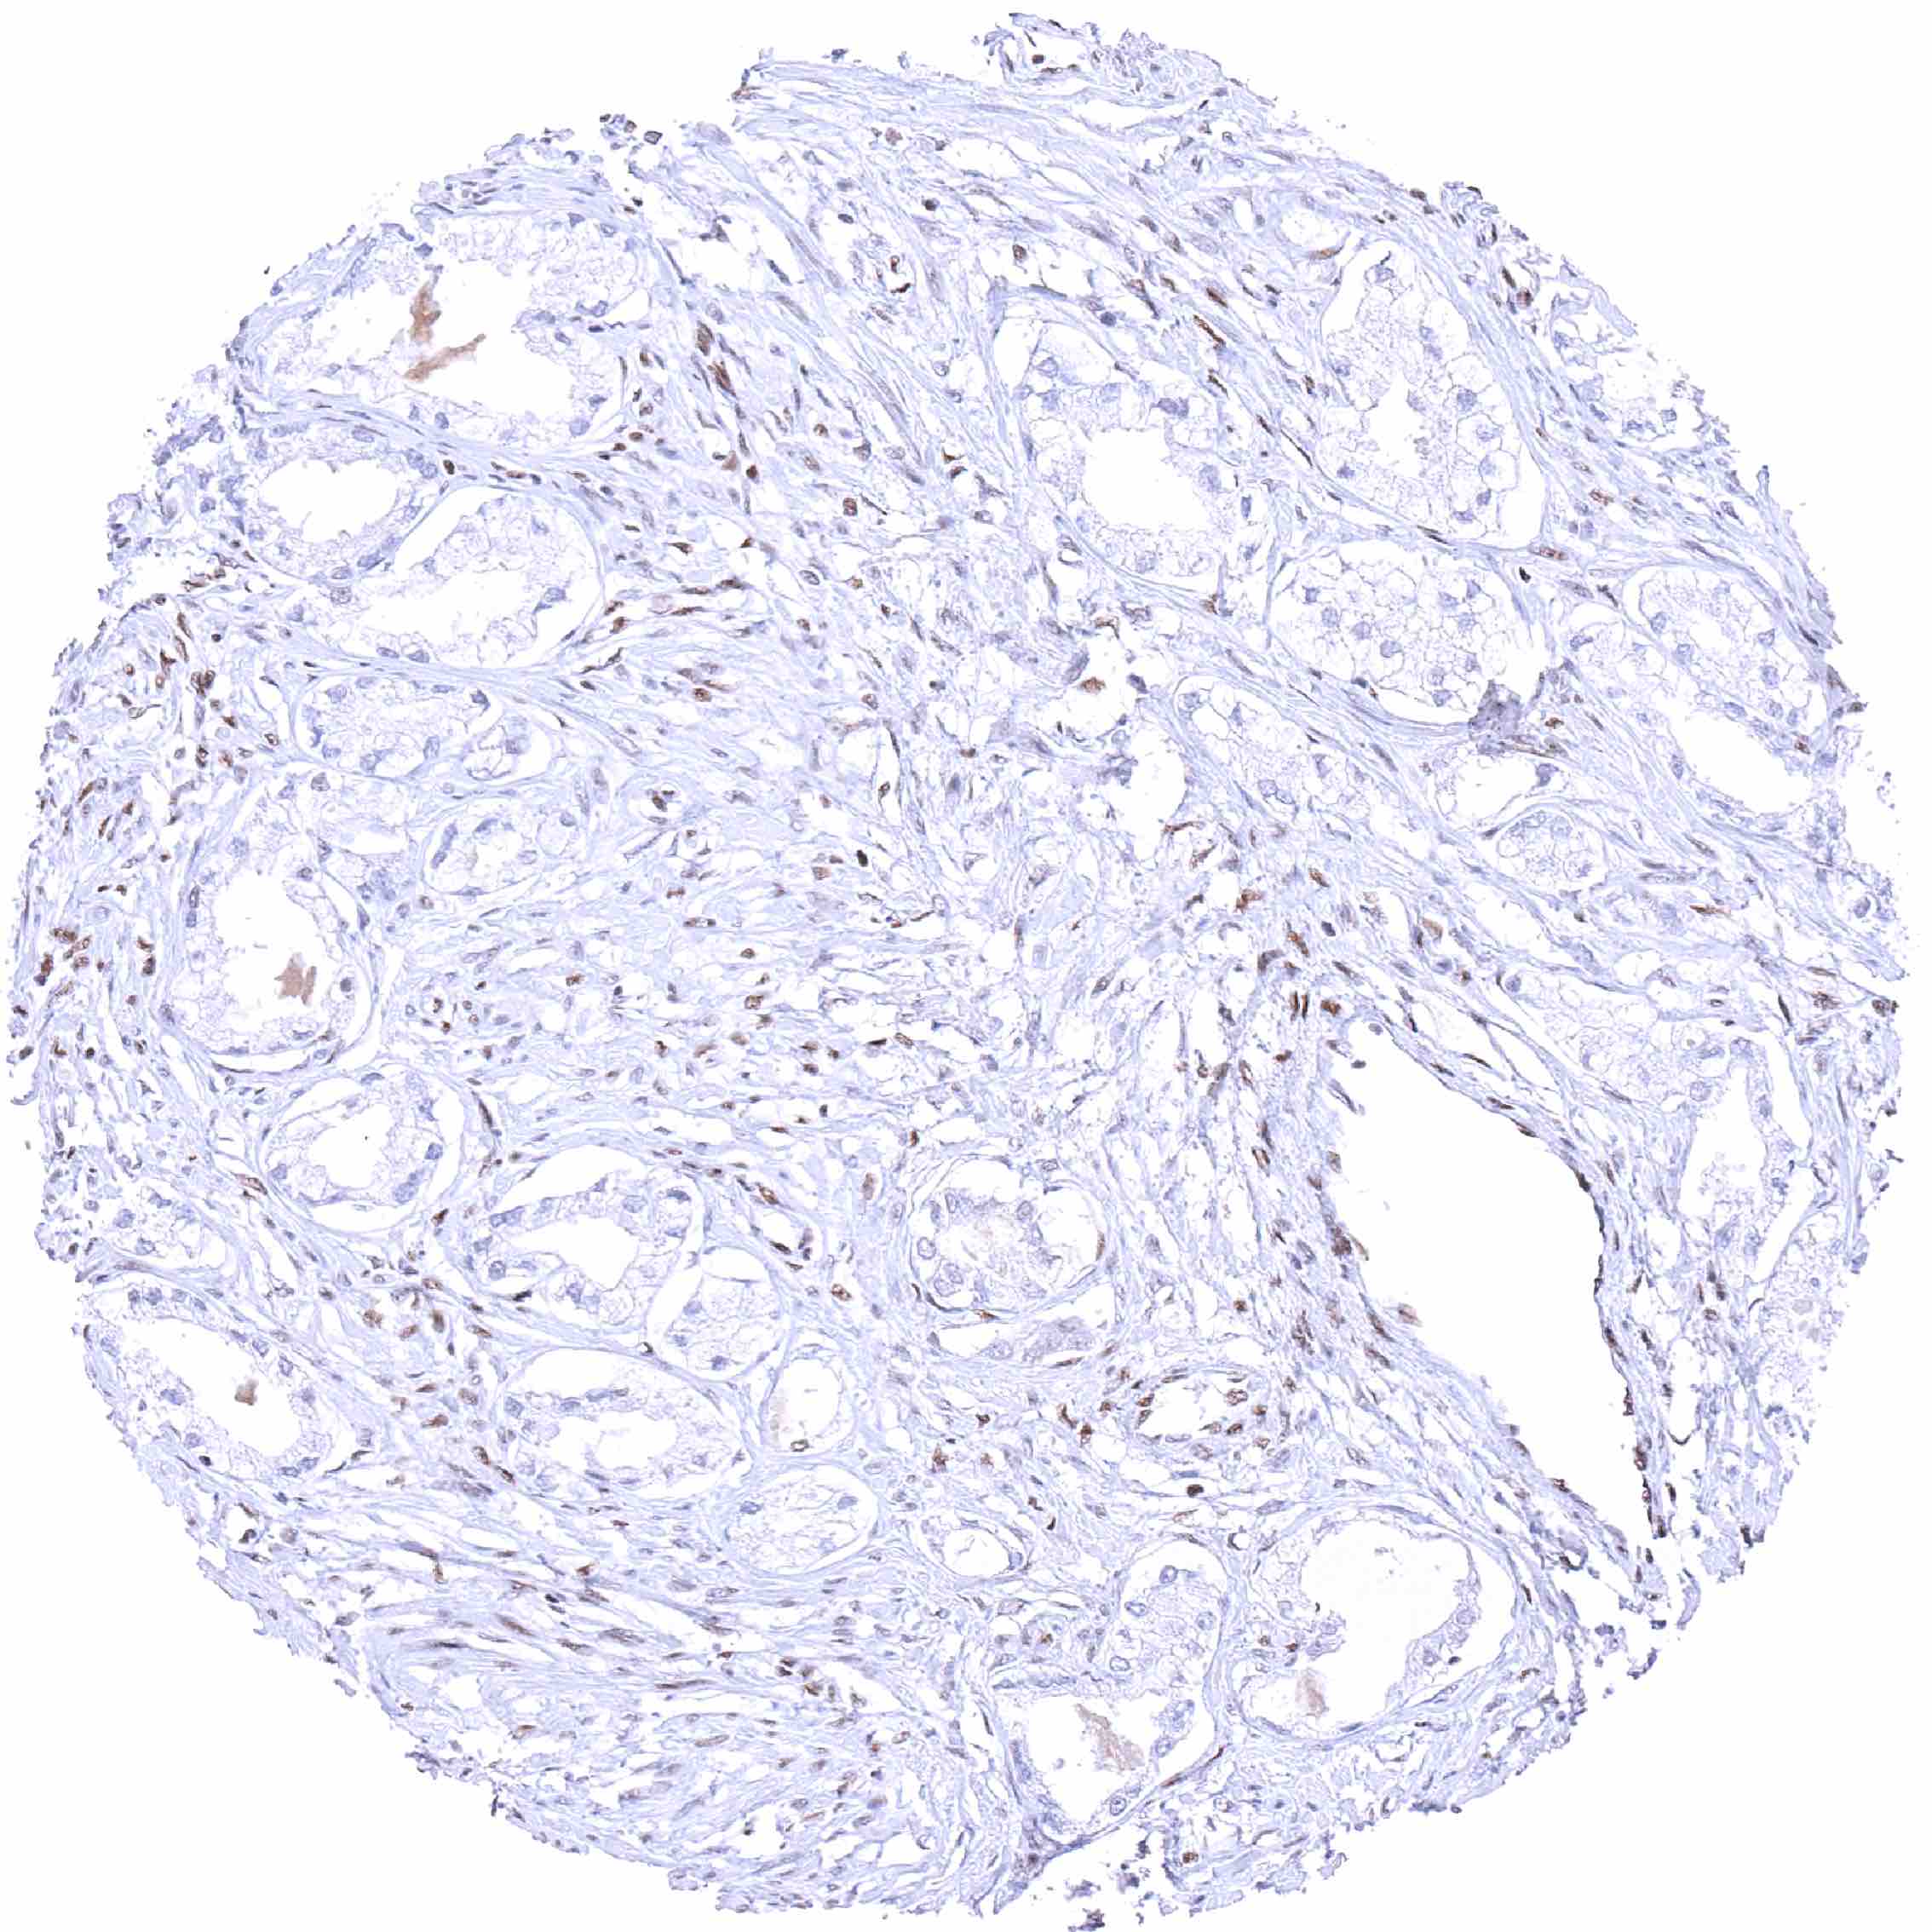

Prostate – BRD4 negative adenocarcinoma (Gleason 3+3=6). A nuclear BRD4 staining is only seen in stroma cells.